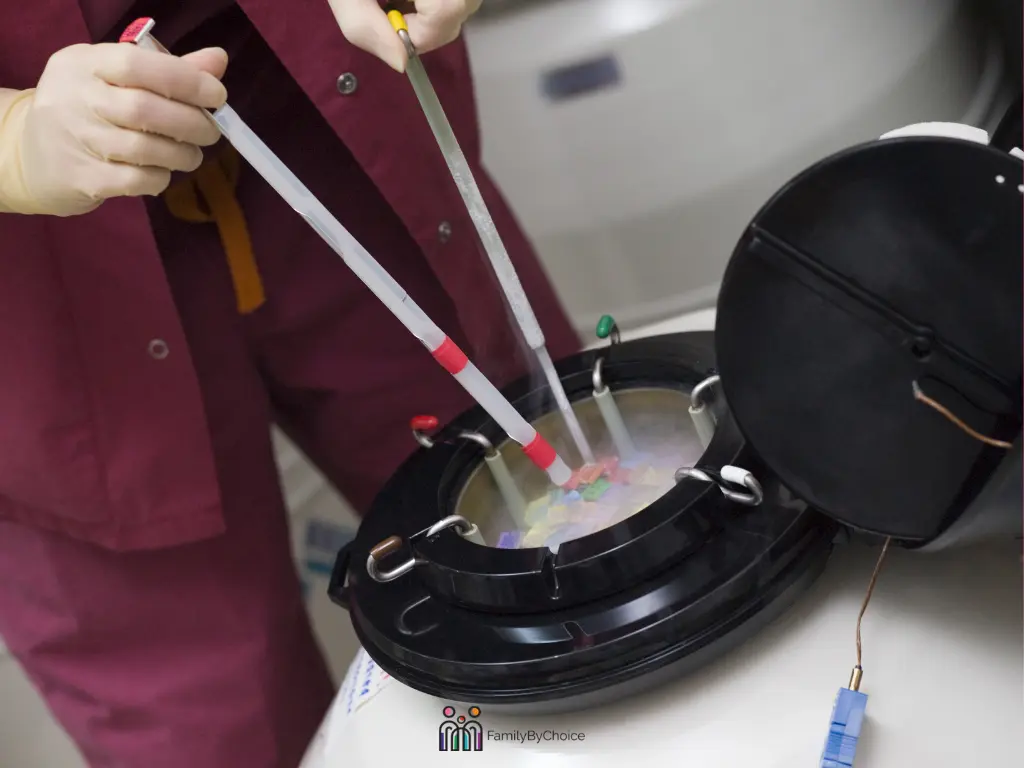

How vitrification changed everything

It’s worth taking a moment to explain what vitrification actually is, because the whole story of frozen eggs is really the story of this one technique.

Before vitrification became standard, freezing eggs was genuinely unreliable. The problem was ice crystals: when cells freeze slowly, water inside them forms crystals that puncture cell membranes and destroy delicate egg structure. Early attempts at egg freezing had poor survival rates and inconsistent results.

Vitrification solved this by freezing at extraordinary speed. Eggs are plunged into liquid nitrogen so fast, dropping from 37°C to -196°C in less than a second, that ice crystals simply never have time to form. Instead, the cellular contents become a glass-like solid, suspending all biological activity. When warmed, the egg returns to its pre-frozen state with minimal damage.

The result: a post-thaw survival rate of approximately 95% for eggs from young donors. That’s not “almost as good as fresh.” That’s genuinely excellent.

One thing to check before committing to frozen: ask your clinic for their specific thaw survival rate and post-thaw fertilization rate. A well-run program should report 90%+ egg survival and fertilization rates of 70–80%. Significant variation exists between clinics, and this matters more than the difference between fresh and frozen in principle.